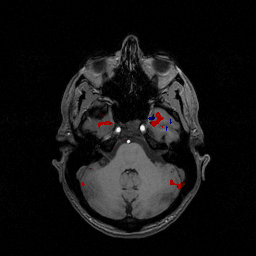

Les zones en couleur(blanc,rouge,jaune,vert) traduisent une augmentation de l'activité du cerveau

Quelques repères sur la carte du cerveau :